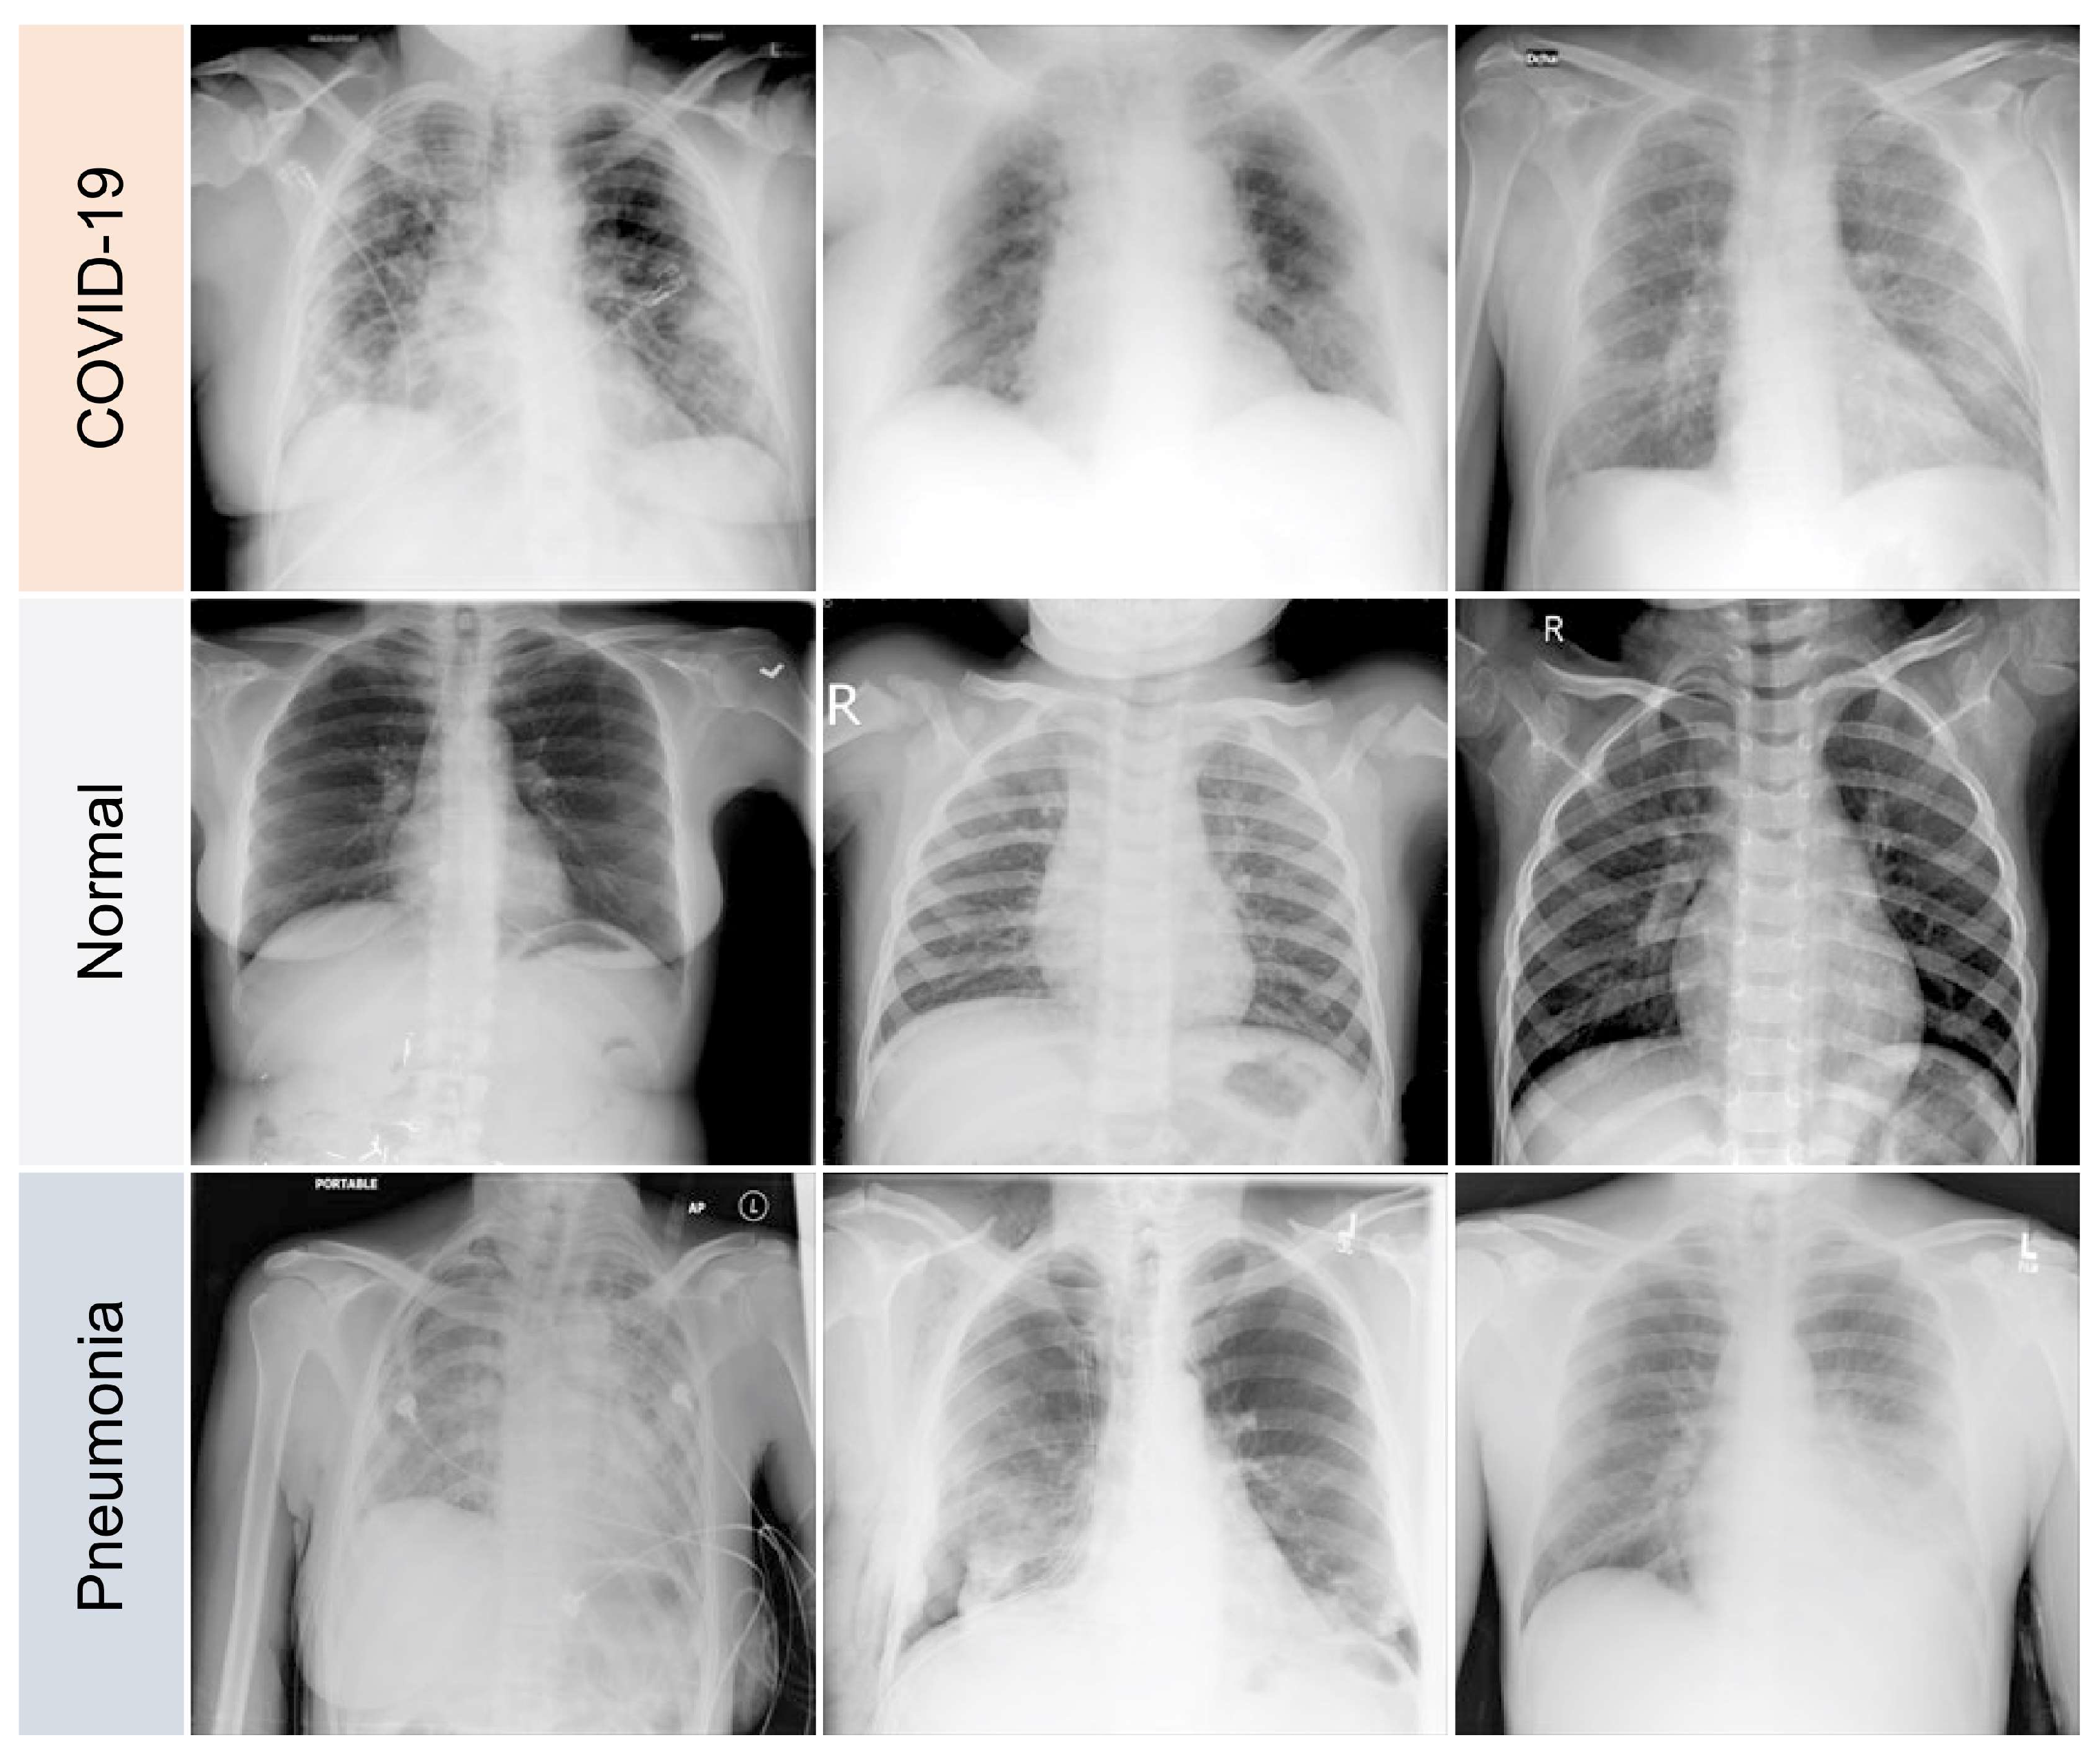

3.1. Data Preparation

- 11,956 COVID-19 samples

- 11,263 cases of pneumonia caused by viruses or bacteria that are not COVID-19

- 10,701 normal (healthy) samples

4.1. Data Processing

- GGOs.

- Odd paving pattern.

- Consolidation of the airspace.

- Thickening of bronchovascular bundles.

- Traction bronchiectasis.

- Reticular opacities.

- Vascular thickness.

- Additional widespread distribution along the bronchovascular bundles.

- Thickness in bronchial wall.